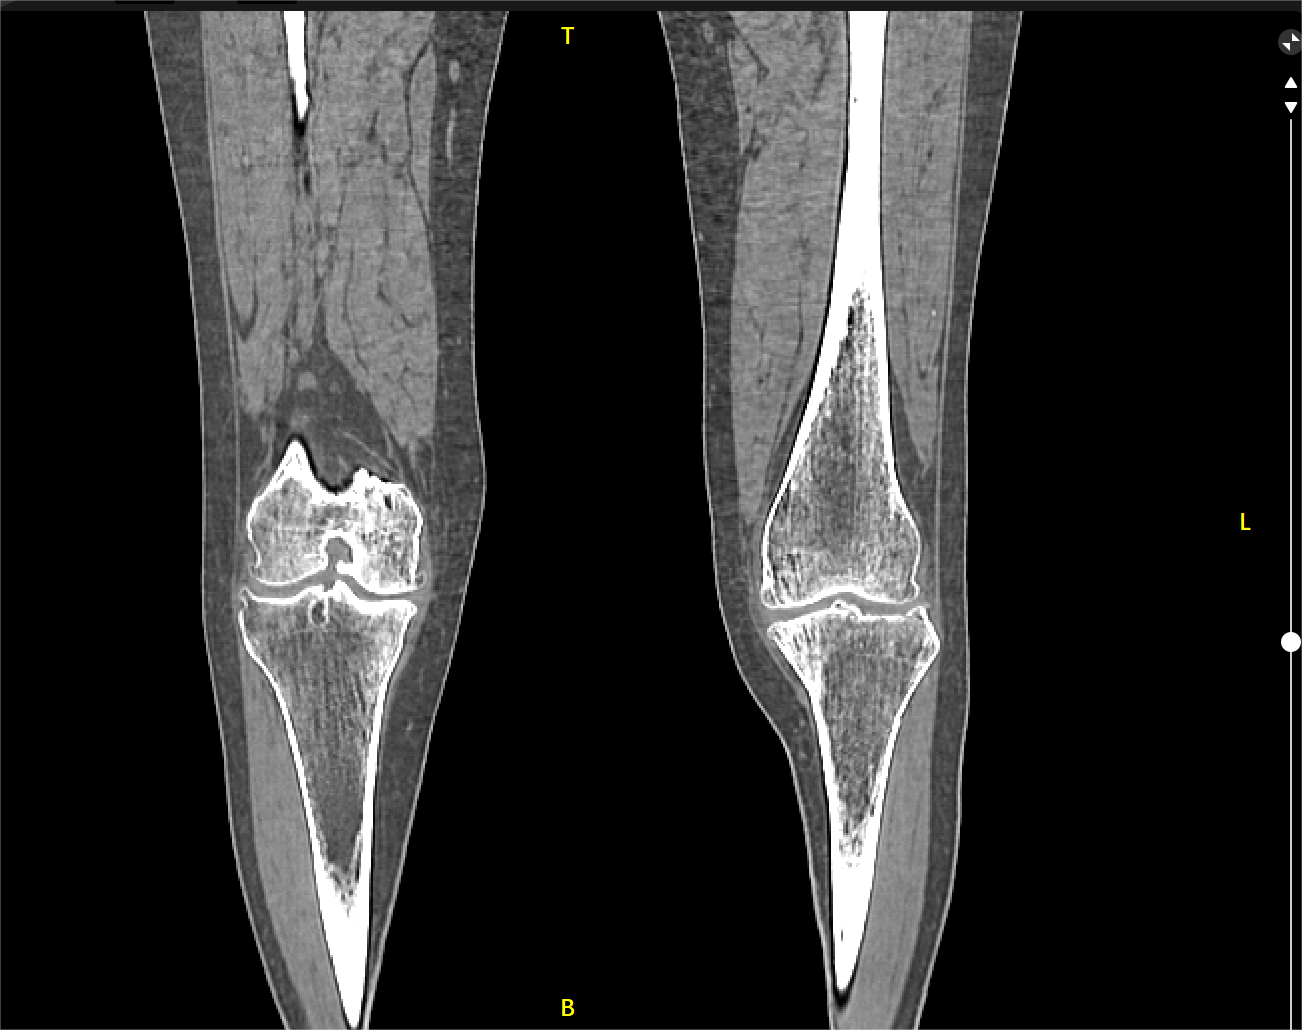

患者劉阿姨,63歲,十余年來飽受膝關(guān)節(jié)疼痛之苦,尤其是上下樓梯時(shí)更覺苦不堪言。近日就診于邵武市立醫(yī)院骨二科,入院進(jìn)行CT檢查,結(jié)果顯示——劉阿姨骨質(zhì)硬化增生改變,膝關(guān)節(jié)內(nèi)翻畸形,診斷為原發(fā)性雙側(cè)膝關(guān)節(jié)病。

▲患者膝關(guān)節(jié)術(shù)前檢查